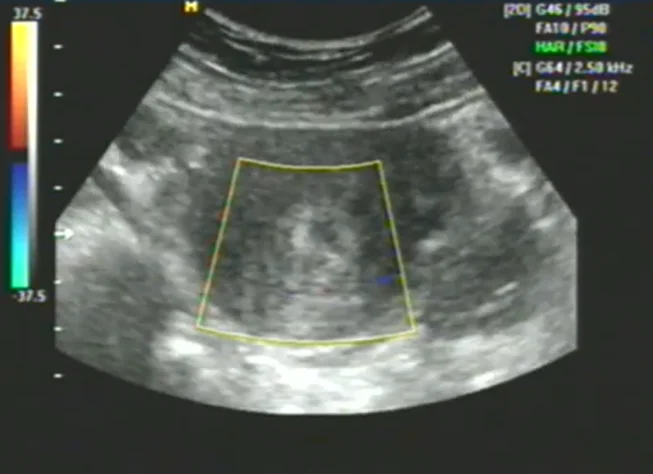

• U xơ tử cung trong thai kỳ (Myoma in Pregnancy)